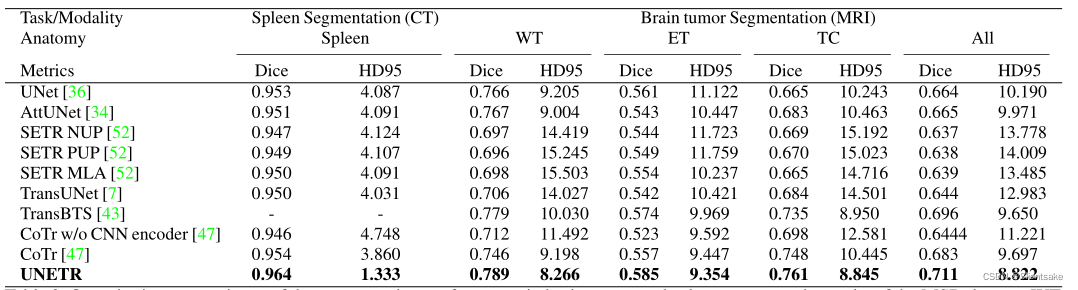

在表2中,在MSD数据集上比较了UNETR与CNN以及基于Transformers的方法在脑肿瘤和脾脏分割任务中的性能。在脑分割方面,UNETR在所有语义类上的平均表现比最接近的基线高出1.5%。特别是,UNETR在分割肿瘤核心(TC)分区域方面表现得相当好。同样,在脾脏分割方面,UNETR在Dice评分方面的表现比最佳竞争方法高出至少1.0%。

表2:定量比较了MSD数据集在脑肿瘤和脾脏分割任务中的分割性能。WT、ET和TC分别表示全肿瘤、增强肿瘤和肿瘤核心子区域。